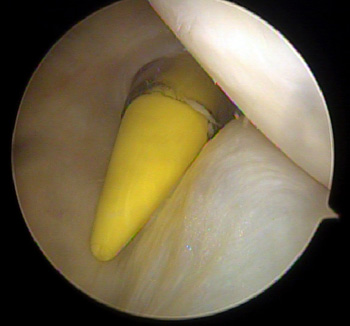

maestu1_fig6

Figura 6: vista artroscópica desde portal anterolateral de pasajes injertos en una rodilla izquierda.